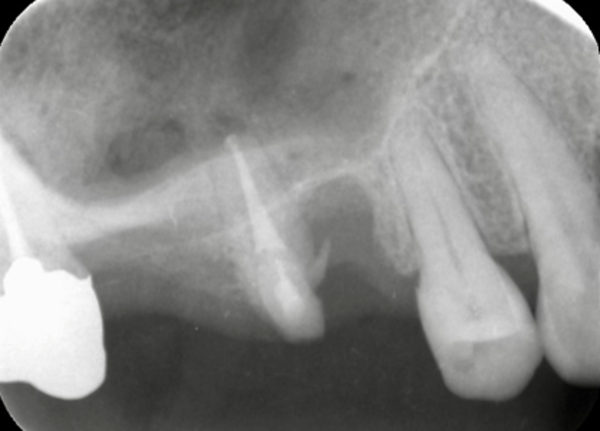

その後、奥から3番目の歯の根管治療を開始しました。しかし3本ある根管のうち1本が破折してしまっていることが判明したため、破折した根のみを抜歯し、残りの2本の根管を治療しました。

写真は根管治療終了時のものです。抜歯部位は骨がかなり薄く、このままではインプラント治療が困難な状態でした。